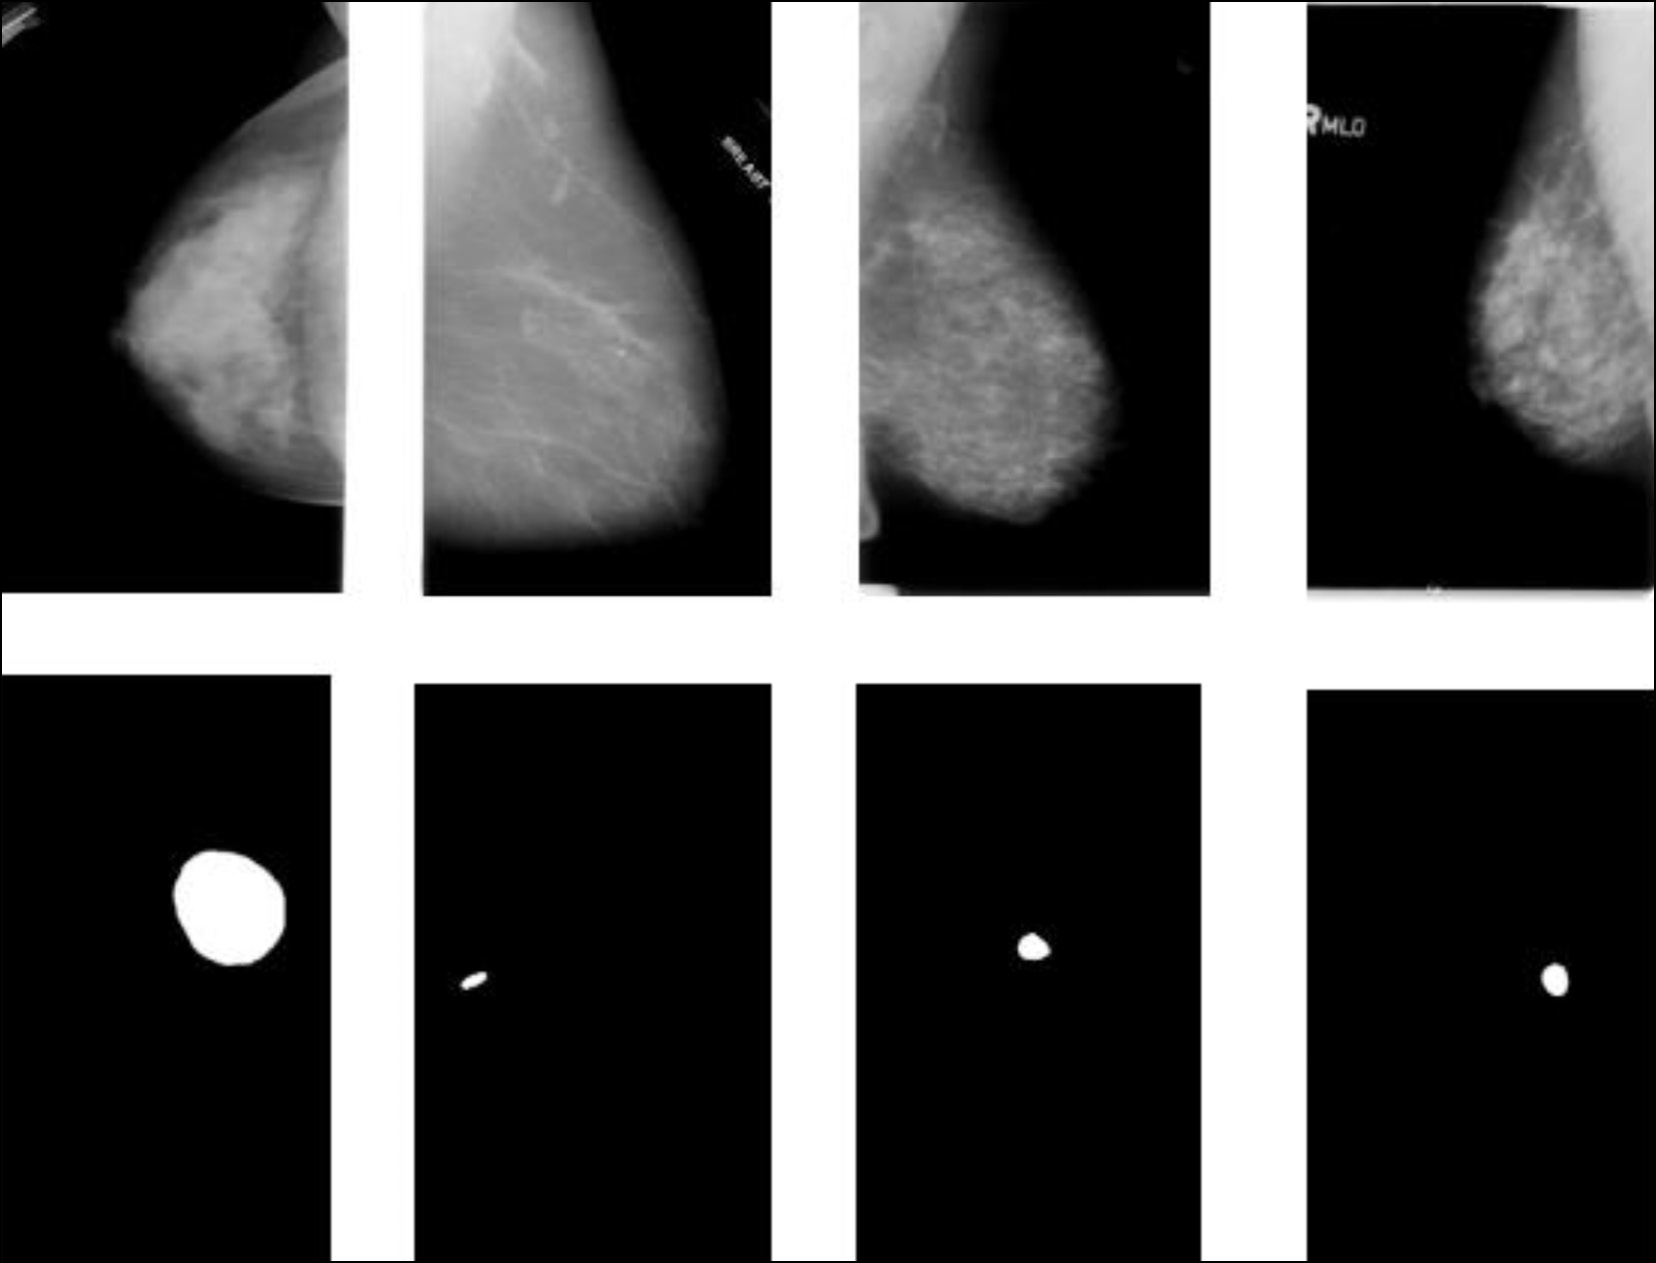

利用机器学习方法诊断乳腺癌

摘要

最近几年,机器学习方法在诊断领域,特别是对乳腺癌的检测受到越来越多的关注。

文章从三个方面分析了当前致力于在乳腺癌诊断中使用机器学习方法的研究:用于解决现代乳腺癌诊断中出现的辅助任务,作为初步诊断决策的患者病情智能评估,以及确定乳腺癌的风险因素。文章从三个方面分析了机器学习方法在乳腺癌诊断中的应用现状:解决现代乳腺癌诊断中出现的辅助课题,智能评估患者病情初步诊断决策,以及确定乳腺癌的风险因素。

分析表明,利用机器学习方法诊断乳腺癌为提高诊断的准确性和效率提供巨大的可能性,并且还可以完成其他额外任务。

文献分析结果,确定了用作机器学习方法中输入数据的特征。今后,收集到的信息将用于构建一个利用机器学习方法诊断乳腺癌的特征系统。